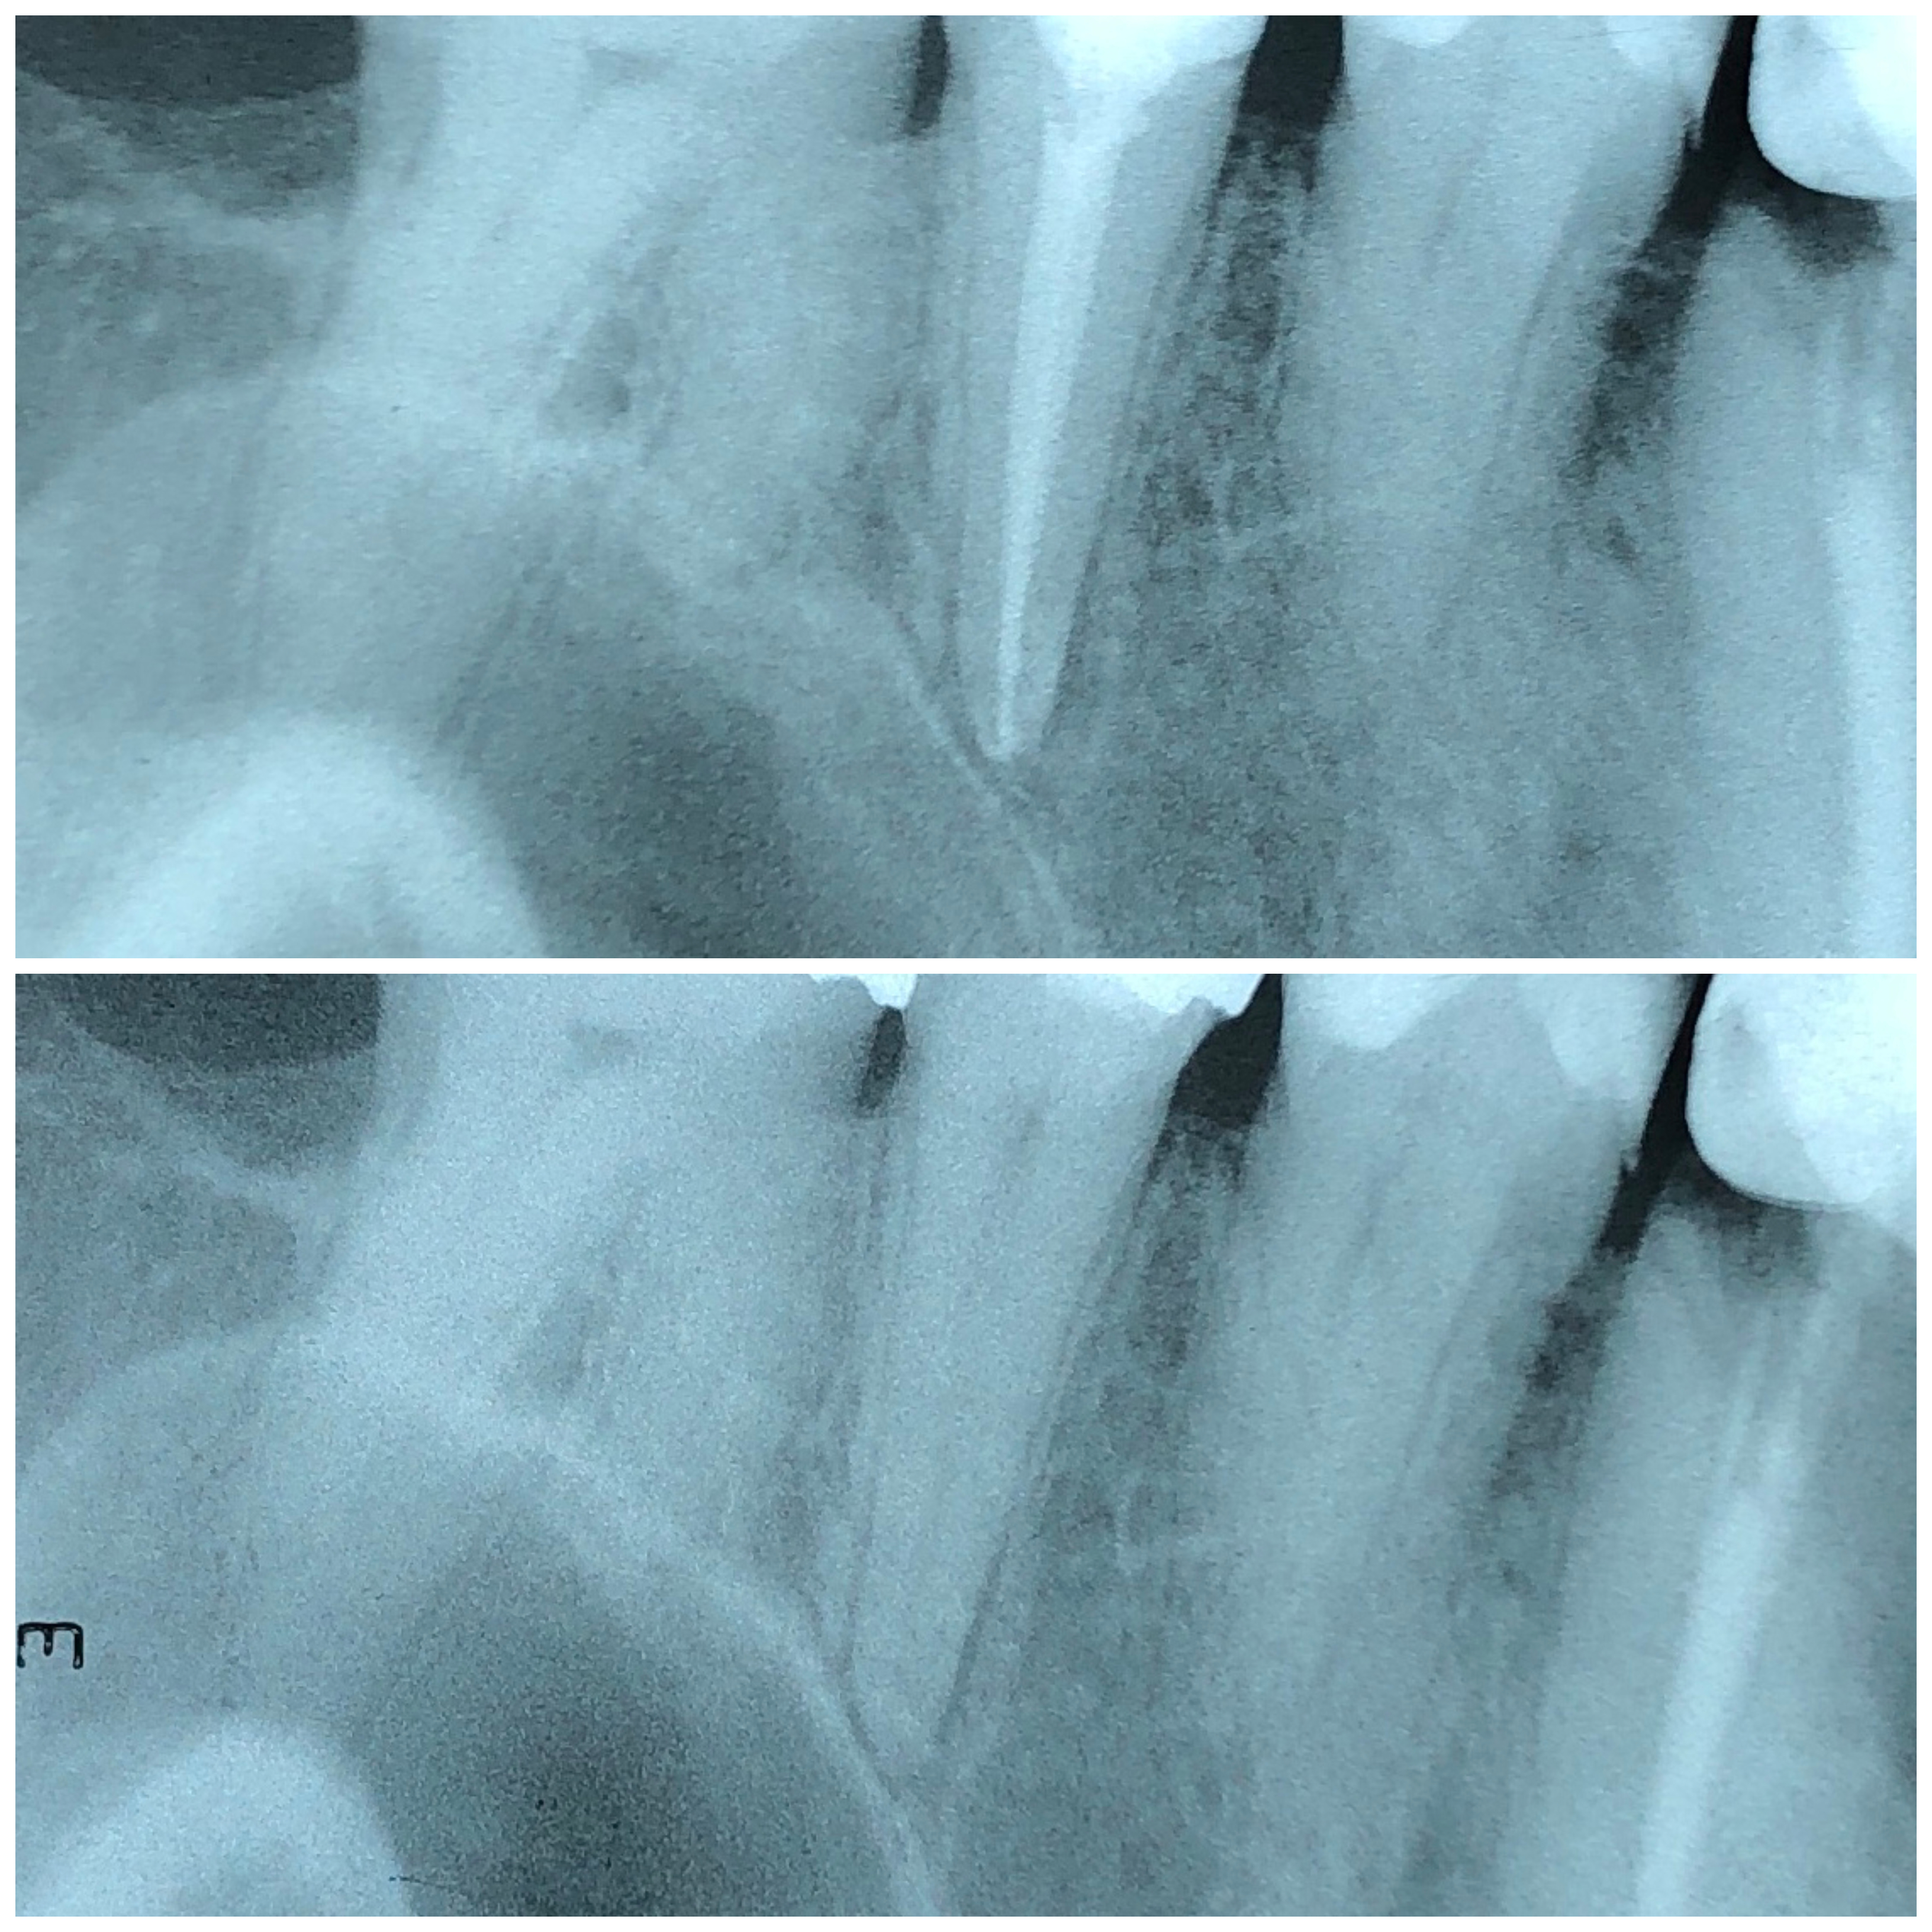

Endodontska terapija započinje uklanjanjem karijesom zahvaćenog zubnog tkiva, nakon čega se odstranjuje upaljena zubna pulpa te se kemijski i mehanički čisti zubni kanal radi uklanjanja bakterija i inficiranog dentina.

Ključ uspješnog liječenja je u primjeni strojne umjesto ručne obrade kanala.

Zato se u našoj ordinaciji primjenjuje najnoviji i tehnološki najmoderniji sustav strojne endodoncije – sustav Reciproc.

Reciproc predstavlja potpuno novi koncept u liječenju korijenskih kanala zuba. Postupak u kojem se primjenjuje ovaj sustav potpuno je siguran, brz, jednostavan i bezbolan. U većini slučajeva za liječenje zuba dovoljan je jedan posjet ordinaciji.